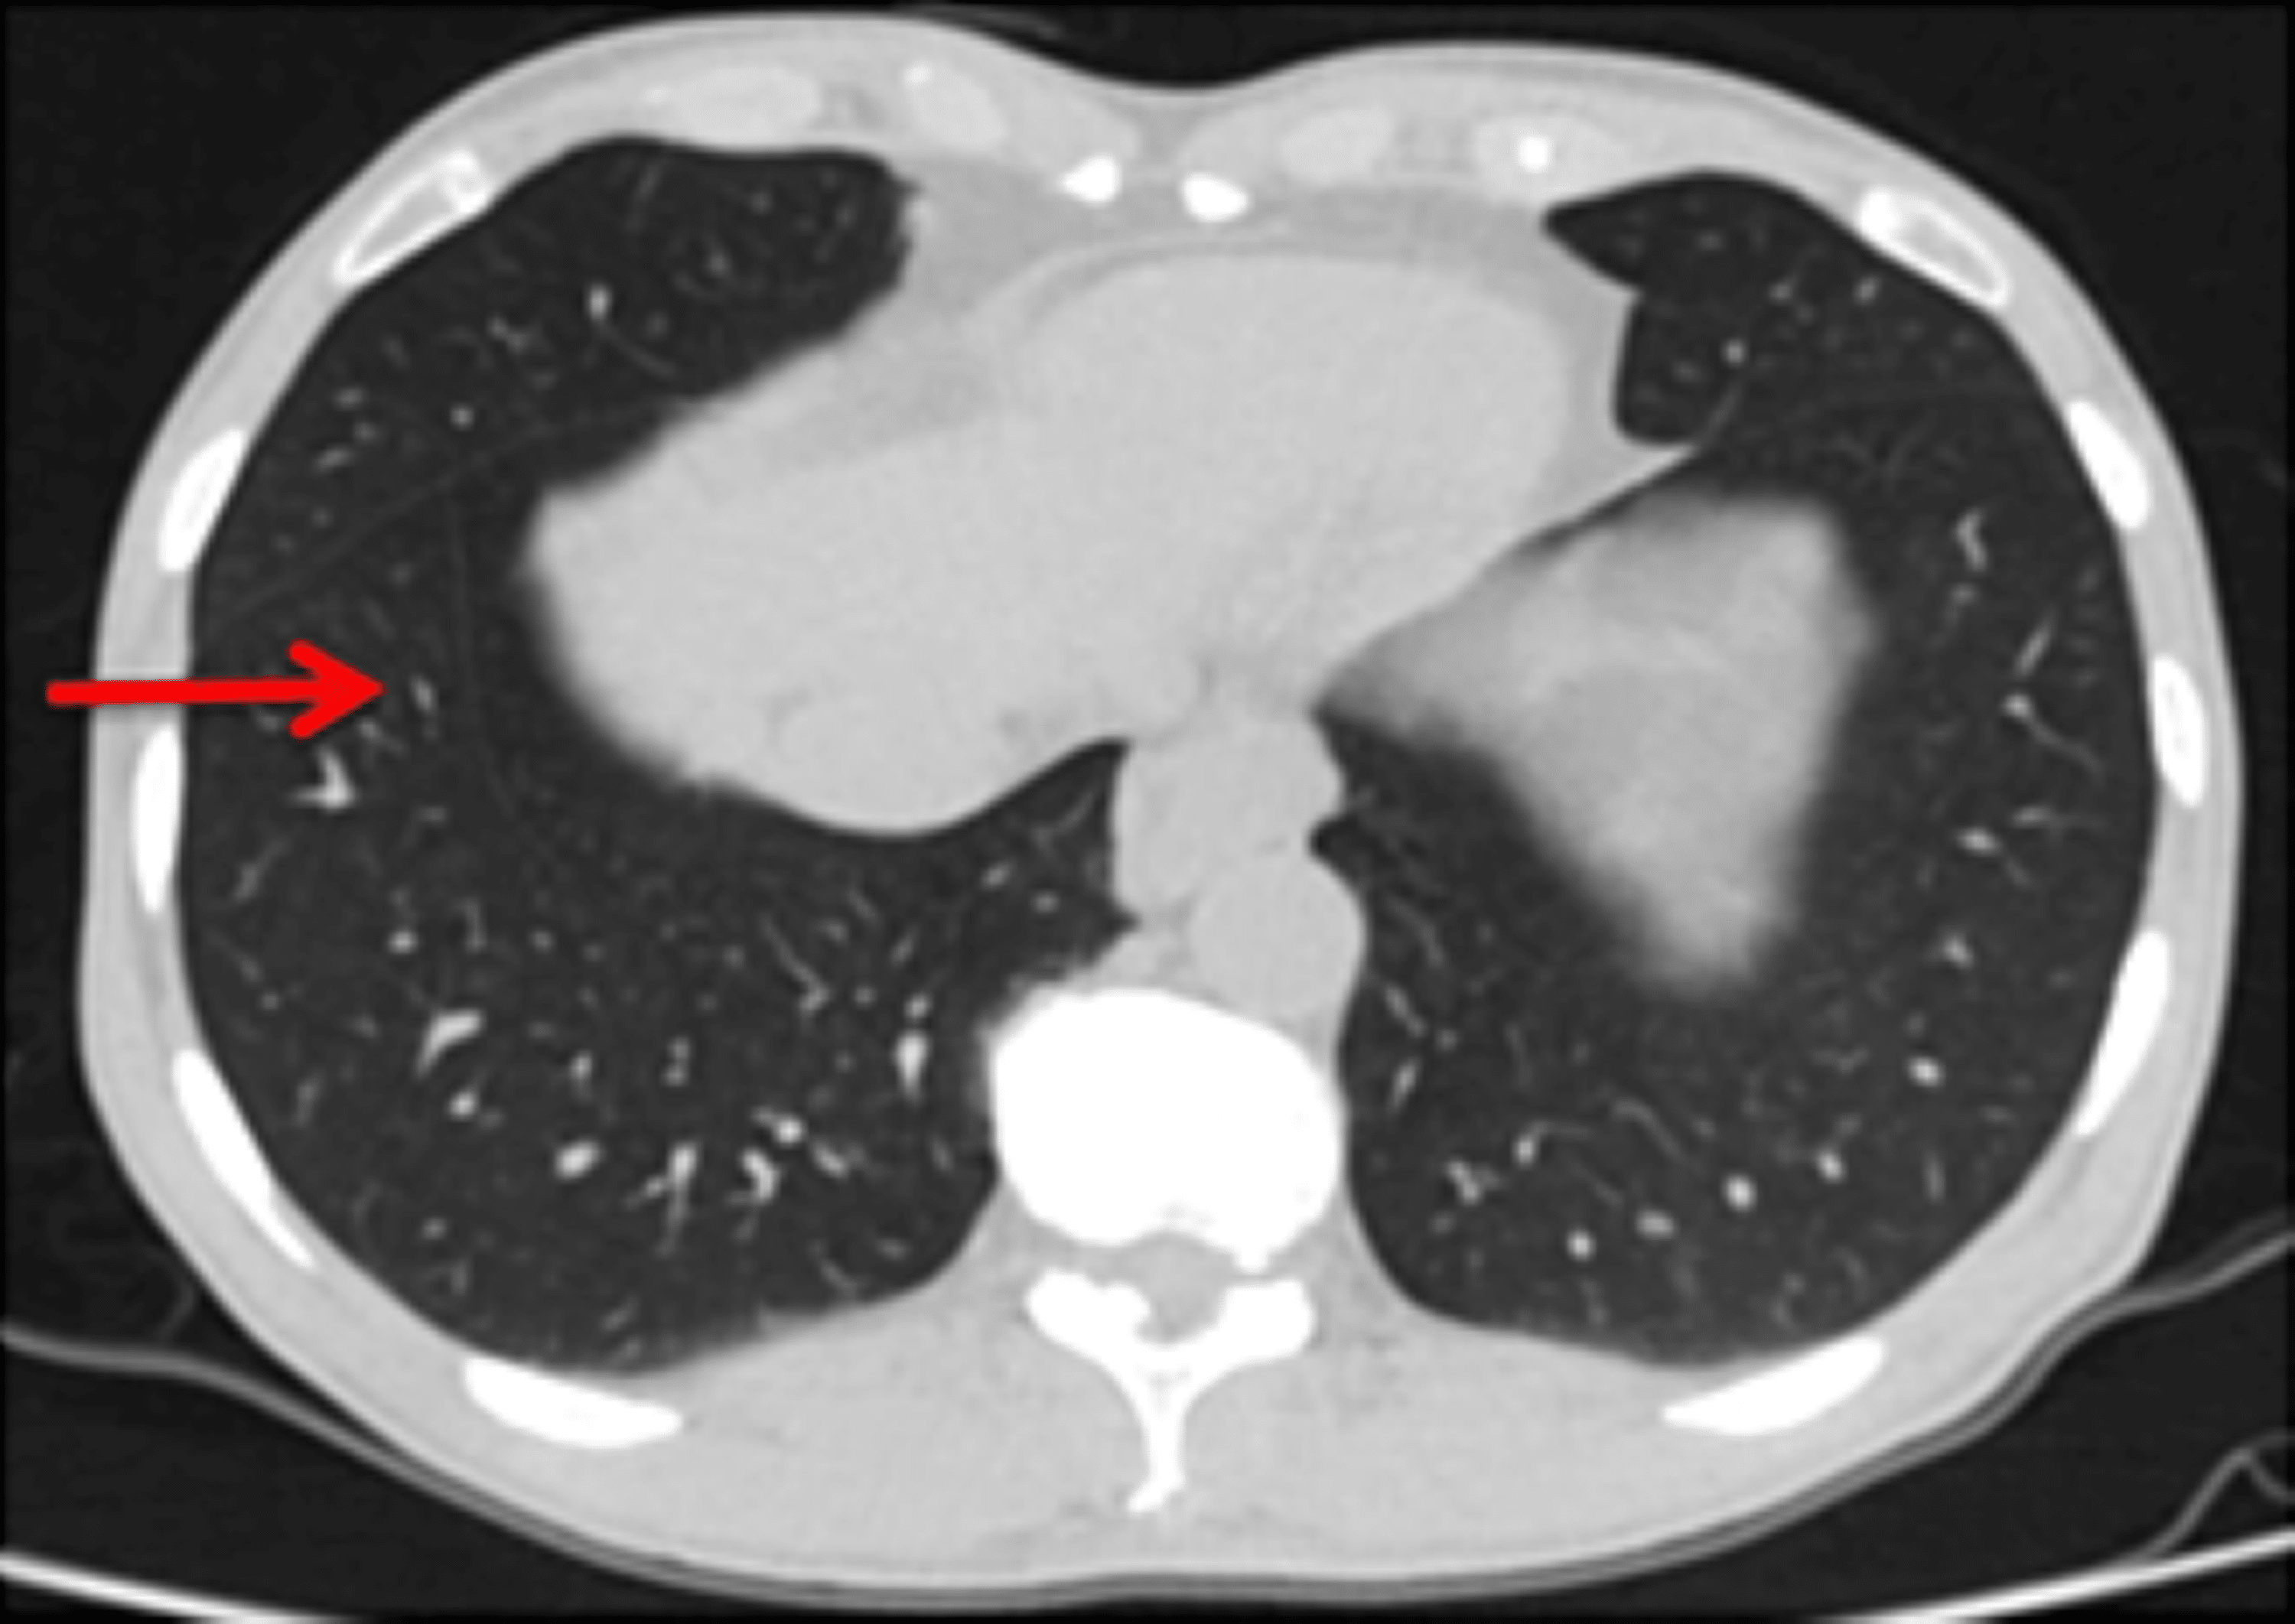

A patient with ‘left middle lung lobe’

From www.pneumon.org

A patient with ‘left middle lung lobe’ Accessory Pulmonary Fissures Learn about the anatomy and imaging of accessory fissures of the lung, including the azygos fissure. Accessory fissures of the lung usually occur at the borders of bronchopulmonary segments. This article has been cited by: They are common normal variants but are less. Find out how to distinguish them from fibrotic. Accessory fissures of the lung. Refilwe seleka, megan petersen,. Accessory Pulmonary Fissures.